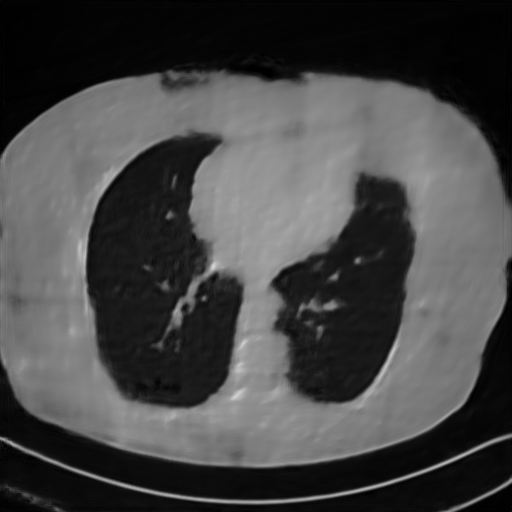

Fig. 4 presents the reconstruction results and residual images obtained by different methods for limited-angle reconstruction. As can be seen, the learning-based methods outperform the direct method and TV model, which exhibit serious artifacts in the missing angle region. Although the denoiser introduced by the FBP-Unet can somehow deal with the noises, the result still presents obvious artifacts. Compared to the SIPID, PD-net and FSR-nets, our LRIP-net1/2 can better preserve the image details and edges with less information left in the residual images. Thus, both the quantitative and qualitative results confirm that the low-to-high double-resolution strategy can improve the reconstruction accuracy for the limited-angle reconstruction problem.

We observe that the low-resolution image prior plays an important role in our method. More specifically, we compare the results of our LRIP-net with respect to different low-resolution priors, which are obtained by down-sampling rate of 1/2, 1/4, and 1/8, respectively. As can be seen in Table III, the best reconstruction results are obtained with the image prior reconstructed by the down-sampling rate of for 150∘, 120∘ and 90∘ limited-angle reconstruction. The visual comparison based on different image priors are also provided in Fig. 5, where obviously less artifacts are left in the reconstruction image by LRIP-net1/8. By comparing the running time, it is easy to see that the smaller the low-resolution image prior, the faster the LRIP-net works.